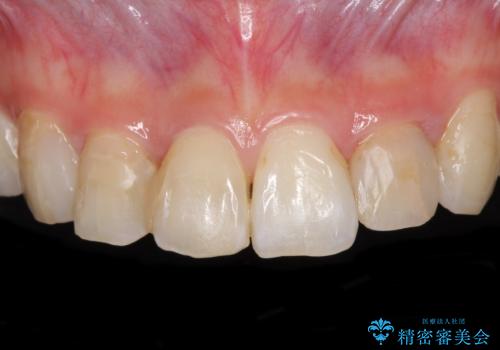

- コンポジットレジンによる治療で継ぎ接ぎだらけになってしまった前歯を綺麗にしたいとのことで来院された患者様です。

必要に応じて根管治療を行い、前歯6歯をオールセラミッククラウンで補綴することとしました。

治療途中に出産を迎えるため、下顎前歯のデコボコを部分矯正で改善し、上下前歯を綺麗に仕上げることとしました。